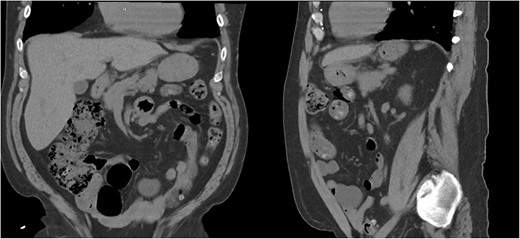

A 55-year-old male underwent lung cancer screening with a chest CT scan (Fig. 1) and was incidentally found to have an anterior diaphragmatic hernia just inferior to the sternum.

Approximately ten years prior, he had undergone coronary artery bypass surgery (CABG) with a xiphoidectomy. His symptoms at the time of the CT were right upper quadrant pain and epigastric fullness. He was referred for outpatient surgical evaluation. Shortly after the initial surgical assessment, he presented to the emergency department with gastric outlet obstruction. An abdominal CT was performed, showing a right-sided type 4 anterior diaphragmatic hernia with herniation of the antrum and pylorus causing the obstruction (Fig. 2). A loop of the transverse colon was also herniated into the thorax but without colonic obstruction.

Right-sided type 4 anterior diaphragmatic hernia with antrum and pylorus herniation.